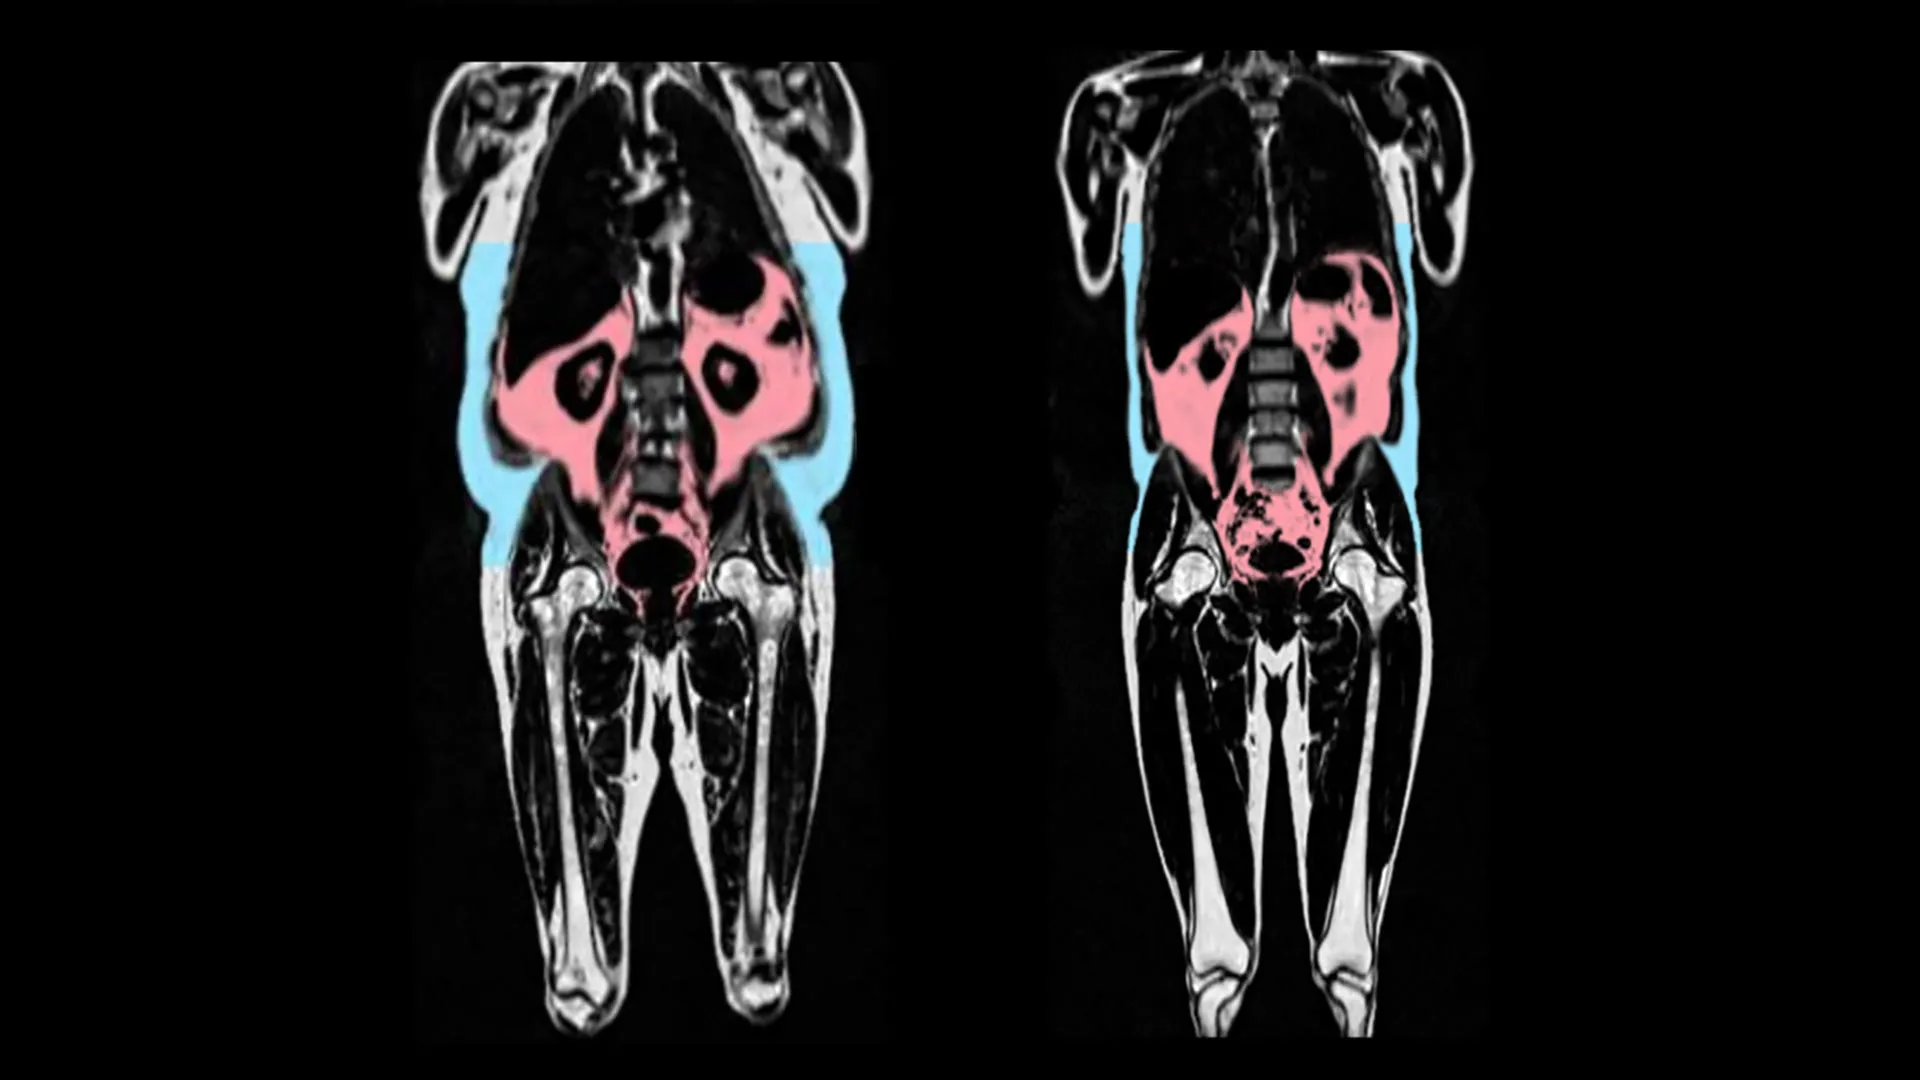

兩張核磁共振掃描圖,顯示左側的人擁有更多的內臟脂肪(紅色)和皮下脂肪(藍色)。圖片來源:AMRA Medical

研究人員發現,心臟加速老化與擁有更多的內臟脂肪組織有關。內臟脂肪組織是位于腹部深處,聚積在胃、腸和肝臟等器官周圍的脂肪。這種脂肪從外部無法看到,因此有些人即使體重正常,也可能有大量的內臟脂肪。